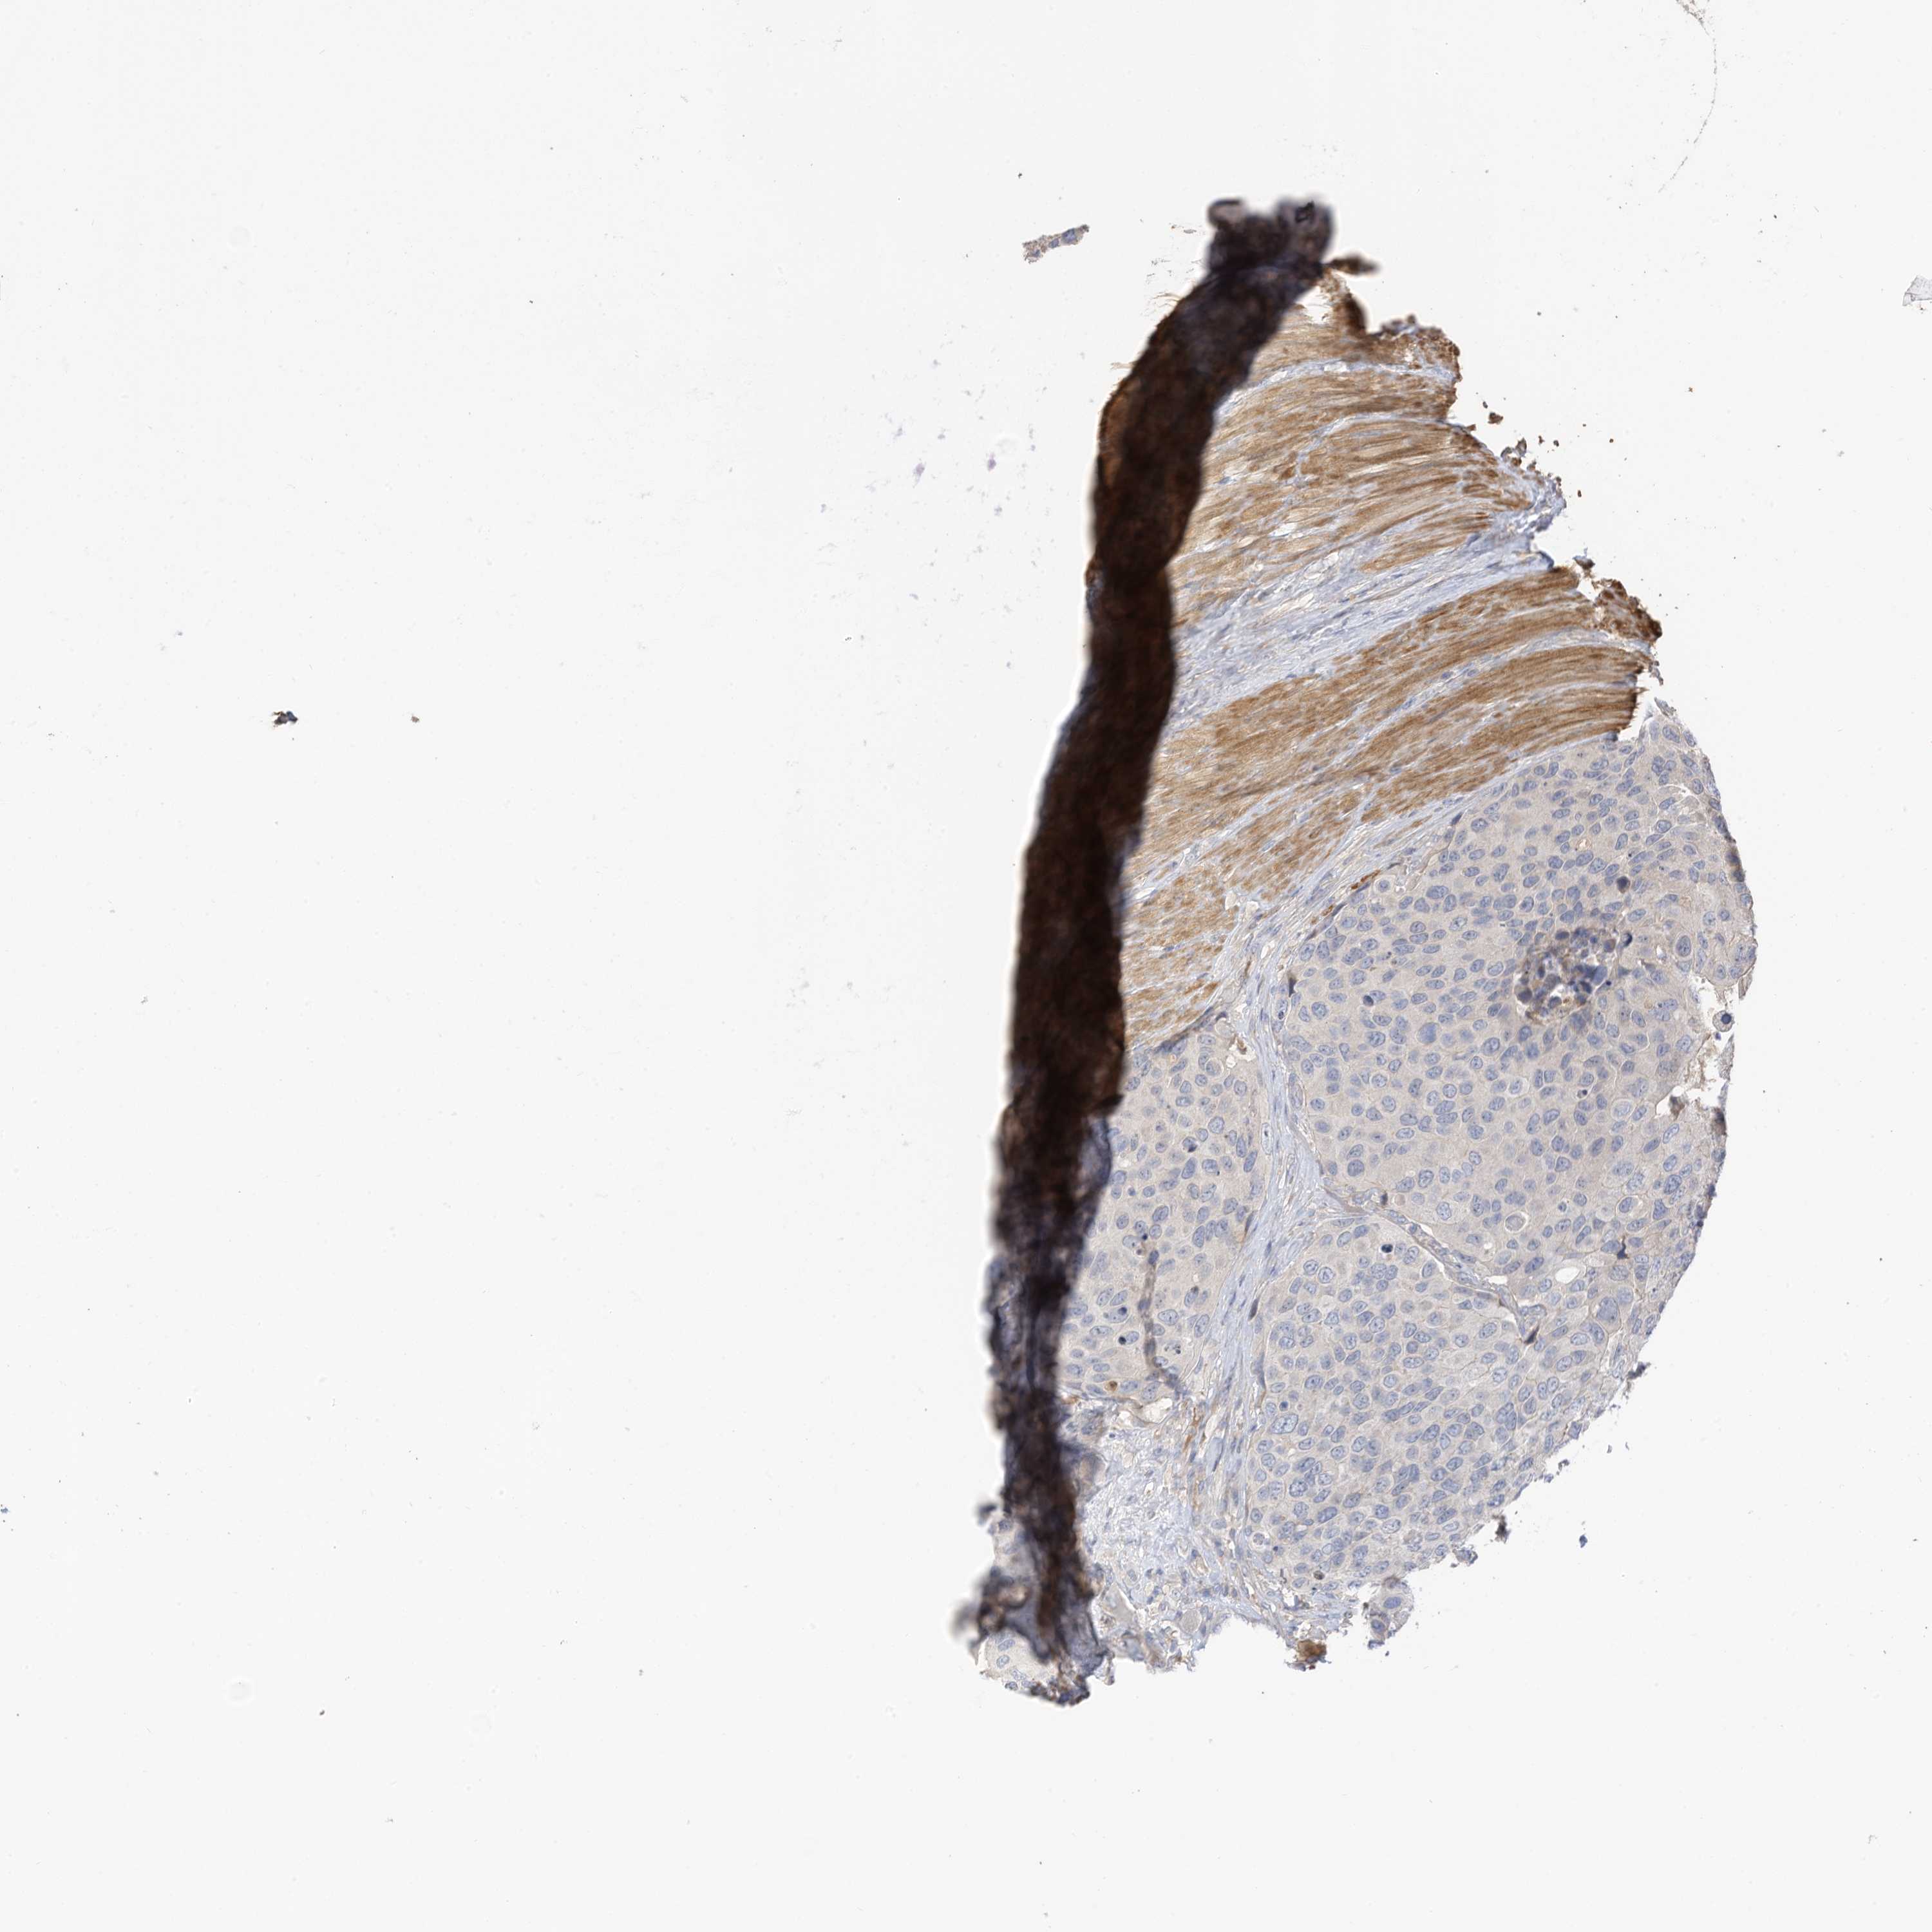

UROTHELIAL CANCER - Protein expressioni

A mouse-over function shows sample information and annotation data. Click on an image to view it in a full screen mode. Samples can be filtered based on level of antibody staining by selecting one or several of the following categories: high, medium, low and not detected. The assay and annotation is described here.

Note that samples used for immunohistochemistry by the Human Protein Atlas do not correspond to samples in the TCGA dataset.

Antibody stainingi

Antibody staining in the annotated cell types in the current human tissue is reported as not detected, low, medium, or high, based on conventional immunohistochemistry profiling in selected tissues. This score is based on the combination of the staining intensity and fraction of stained cells.

Each image is clickable and will lead to virtual microscopy that enables deeper exploration of all samples and also displays staining intensity scores, fraction scores and subcellular localization as well as patient and tissue information for each sample.

Antibody HPA022994

Antibody HPA023065

Urothelial carcinoma, High grade

Urothelial carcinoma, Low grade